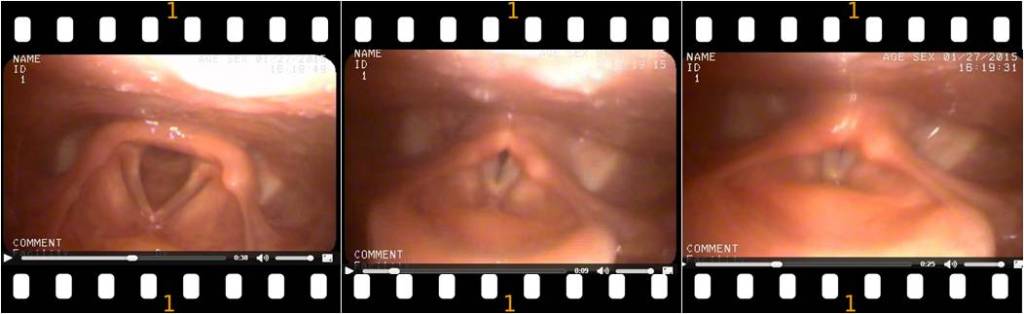

LARYNGOSCOPY

Performed by a Specialist. This is a medical procedure that is used to obtain a view of the vocal folds and the glottis. Typically, a flexible scope is used to view movement of the vocal cords when a patient is symptomatic. Since VCD is usually not usually present after ceasing exercise, our specialist was able to mimic VCD using sounds created by my daughter while the scope was in place.

What is Happening? The black areas in the illustration below show the amount of opening to allow for air to pass: